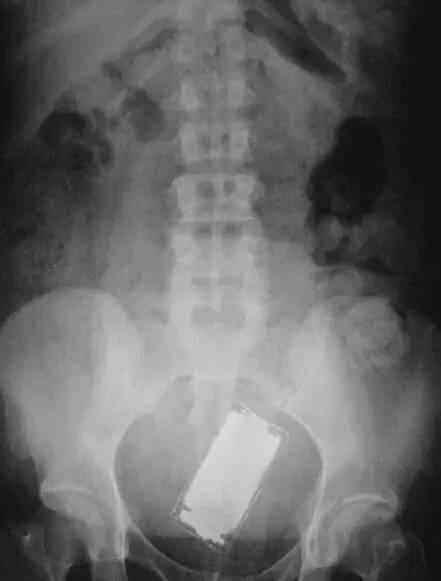

手机也可以塞进去